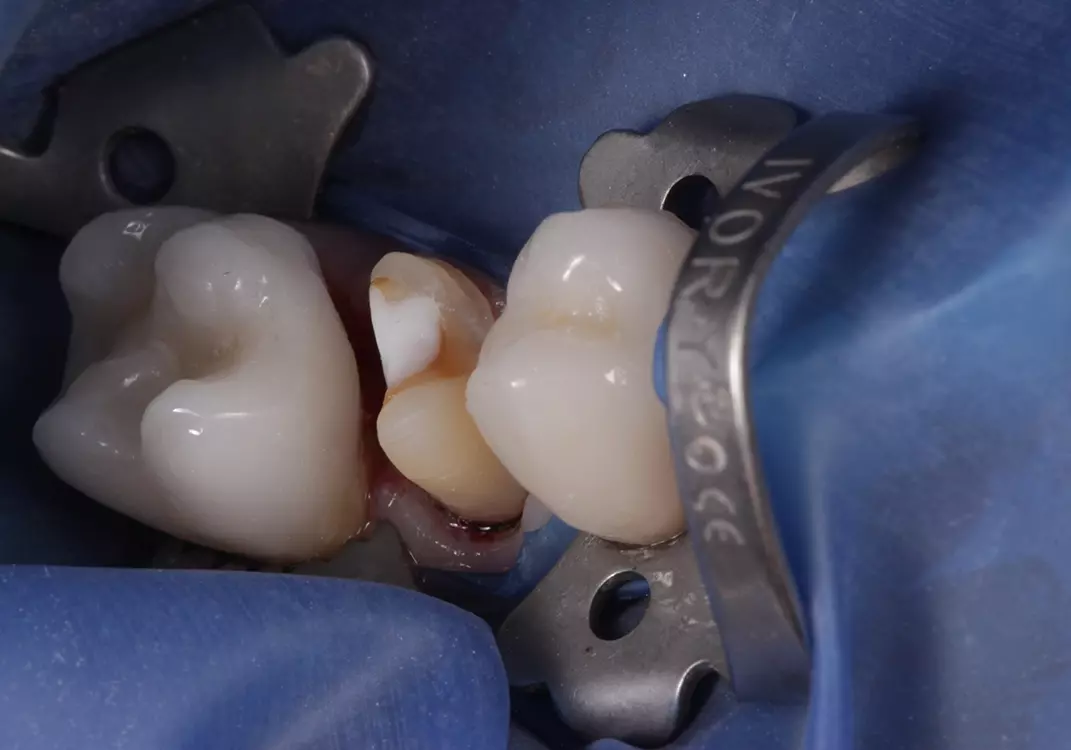

In den darauffolgenden Sitzungen wurden die Zähne 35, 37, 44 und 46 für die definitive Versorgung mit Presskeramikteilkronen versorgt sowie verschraubte Implantatkronen 036 und 045 eingegliedert (Abb. 11). Nach anschließender Präparation für die definitive Versorgung im Oberkieferseitenzahnbereich der Zähne 14 bis 16 sowie 24 bis 26 wurden Presskeramikteilkronen eingegliedert (Abb. 12).